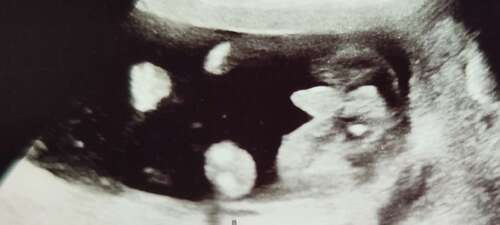

Gestern hat die Ärztin zwischen die Beine geschaut und ich hätte meinen können das ich da einen kleinen pullermann gesehn hab🙈 Aber ich war so unter strom vielleicht wars auch nur die nabelschnur😅🙆🏽♀️

Ah sieht man schon deutlich🙈

Weiß gar nicht wie sicher man das geschlecht in der 15ssw bestimmen kann, bei einem jungen wahrscheinlich einfacher und schneller🙈